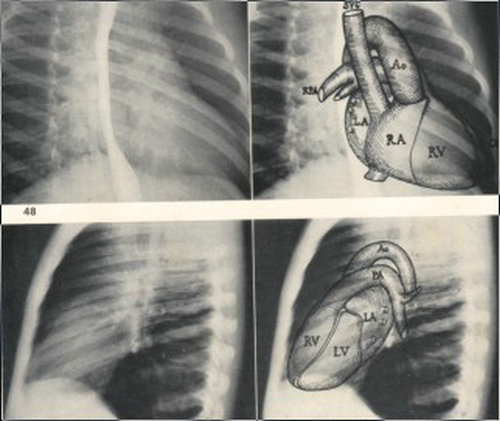

心脏四个基本摄片位-X线